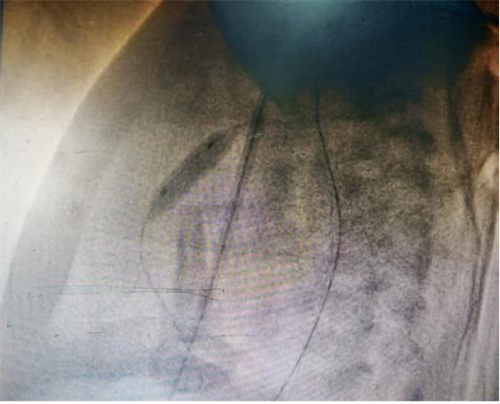

图中为肺动脉球囊扩张即刻,狭窄腰征消失,达到有效扩张

手术室内,麻醉团队为手术精准护航,新生儿科刘红副主任医师全程严密监护生命体征,守住安全底线。小儿心脏科张庆彪主任团队在影像引导下,凭借高超技术,仅依靠一根微导丝建立轨道,成功将球囊导管送至狭窄的肺动脉瓣处。随着球囊的扩张,原本近乎闭锁的瓣膜被成功打开。术后即时测量显示,跨瓣压差从术前的127mmHg大幅降至12mmHg,患儿血氧饱和度随即显著改善,手术宣告成功。